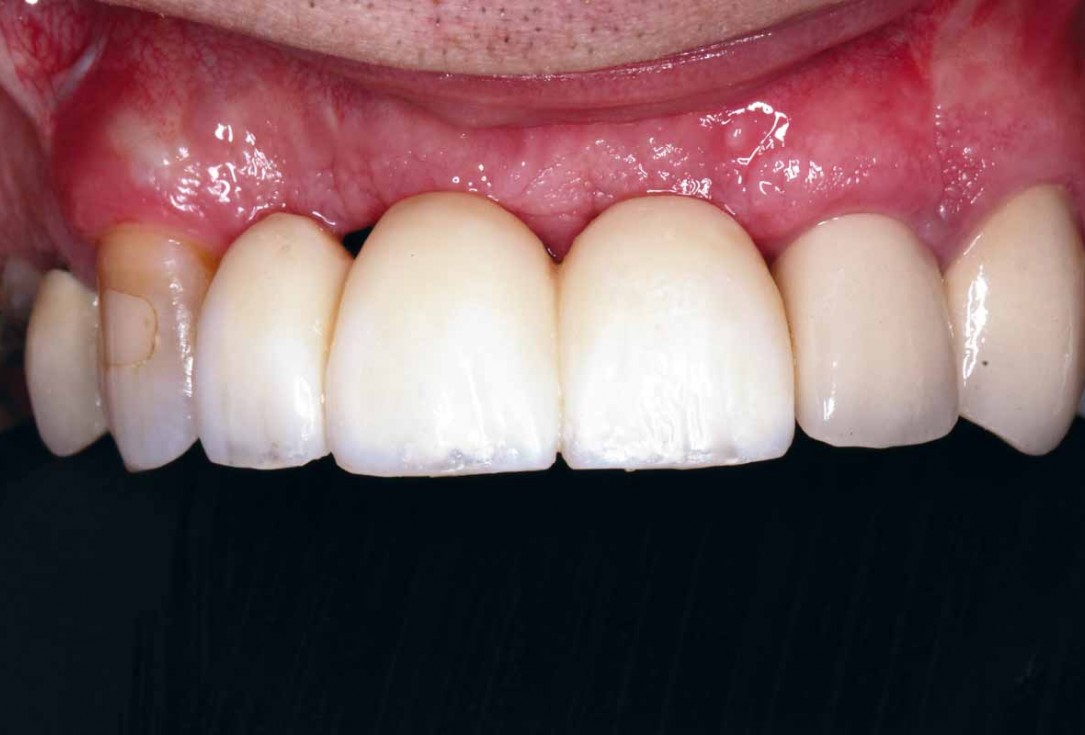

27/27 - Final clinical outcome

GBR and soft tissue augmentation with cerabone® and mucoderm® - H. Maghaireh & V. Ivancheva